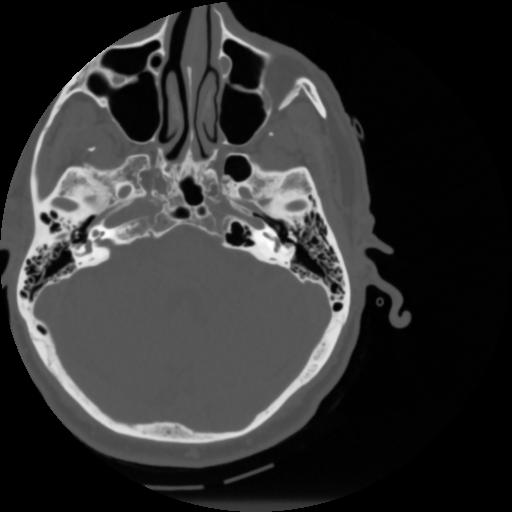

4 CEREBRO,,Vol,0.5,CEREBRO,,